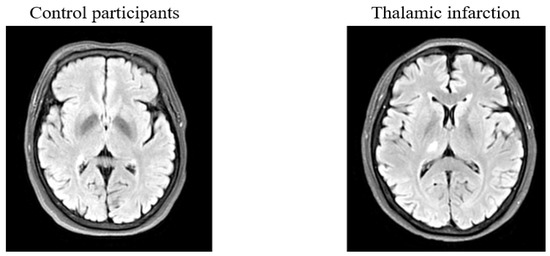

2.2. MRI Acquisition and Procession